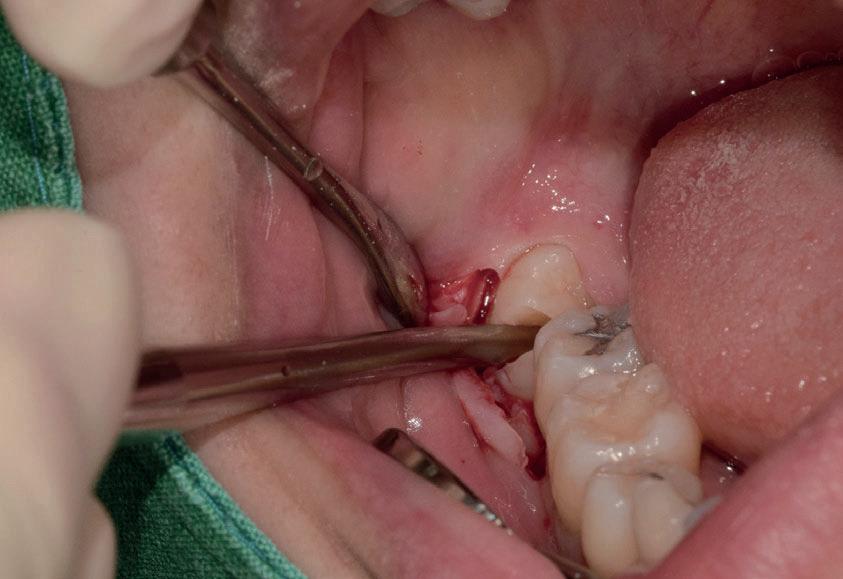

Il seguente caso chirurgico è di un 4.8 mesio-inclinato e parzialmente incluso. Dopo un’incisione a busta, il

dente è stato separato al centro per fare una coronectomia, prima della porzione distale e successivamente della porzione mesiale. Facendo leva quindi è stato possibile rimuovere le radici unite. Figg. 165-172

Figg. 165-172 - Caso 3: tecnica di estrazione con divisione orizzontale utilizzando il manipolo dritto. Fig. 165 Fig. 166 Fig. 167 Fig. 168 Fig. 169 Fig. 170 Fig. 171 Fig. 172